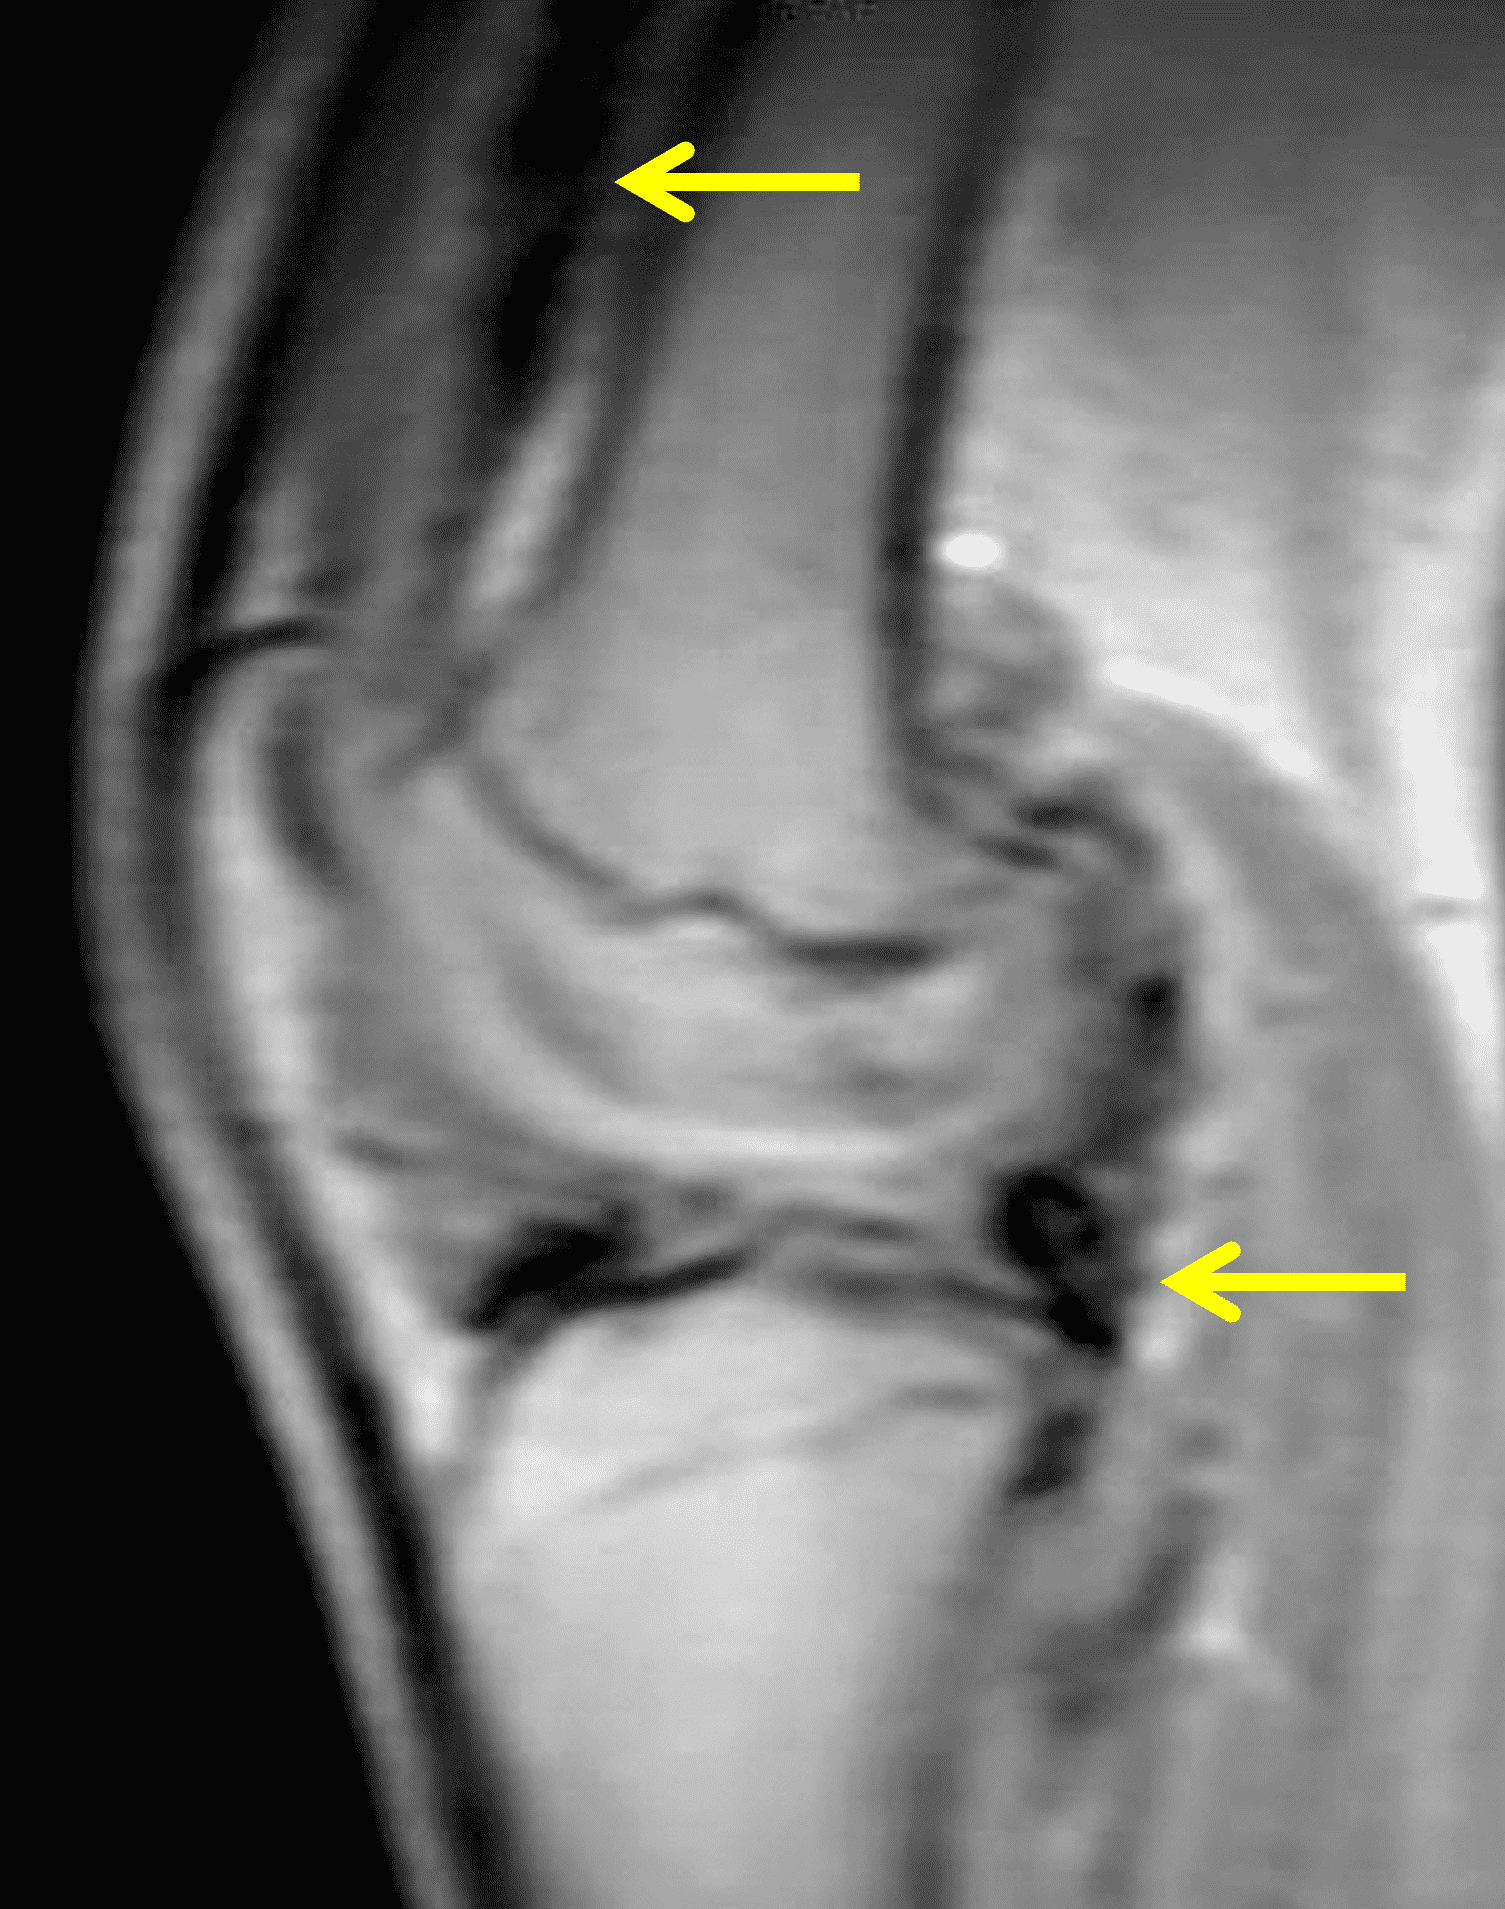

Figure 2: (2A) The coronal image shows a large effusion and severe hypertrophic synovitis (asterisks) in the knee. (2B) On the sagittal image the hypertrophic synovium (asterisks) involves the suprapatellar and infrapatellar recesses as well as the anterior and posterior intercondylar notch. A reactive lymph node (arrow) is present in the popliteal fossa. (2C) The axial image demonstrates myositis (arrows) involving the popliteus and peroneus longus muscles. Note the preserved articular cartilage, lack of erosions, and the absence of subcutaneous or marrow edema.

The causative spirochete invades the synovium, triggering a host inflammatory response that leads to synovial hypertrophy and inflammation, resulting in the characteristic clinical symptoms and imaging findings associated with Lyme arthritis.2 Common MR findings associated with Lyme arthritis include synovitis, joint effusion, popliteal lymphadenopathy, and myositis predominantly involving the popliteus (Figure 4).2,3,9 In contrast to acute septic arthritis due to more common bacteria, subcutaneous edema, marrow edema, erosions, and osteomyelitis are uncommon (Figure 4C).